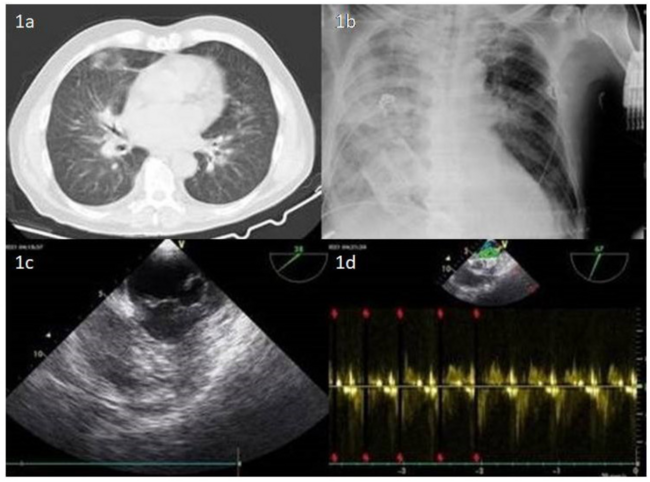

A 72-year-old man with chronic obstructive pulmonary disease (COPD) complained of worsening dyspnea. Physical examination revealed a soft systolic murmur best heard at the apex, third cardiac sound, hypoventilation of the right lung, and bilateral basal crackles. Body temperature was 36.9 °C, blood pressure 140/85 mm Hg, and oxygen saturation was 91%. Leukocytosis and increased C-reactive protein were marked. Chest computed tomography depicted right middle lobe air-bronchogram (Figure 1A). The patient was put on noninvasive positive-pressure ventilation and intravenous antibiotics on the basis of COPD exacerbation. Hemodynamic instability ensued 24 hours later. The patient went cold and wet, hypotensive, and severely tachypneic, and a holosystolic murmur was auscultated. Bedside x-ray showed total right lung opacification (unilateral pulmonary edema) (Figure 1B).

Transesophageal echocardiography (Figure 1C) confirmed cardiogenic shock due to mitral valve (MV) flail of the posterior leaflet, leading to acute MV regurgitation with an asymmetric jet directed toward the septal wall of the left atrium into the right upper pulmonary vein (Figure 1D). Myxomatoid degeneration and prolapse of the P2 scallop of the posterior leaflet due to spontaneous chordae tendinae rupture were evident (Video 1). Conventional ventilation was preferred over independent lung aeration techniques. Utmost caution was paid to avoid dislodgment of the tube into the (pathological) right lung. High positive end-expiratory pressure (PEEP) was required and urgent ultimate cardiothoracic treatment was pursued following an unremarkable coronary angiography (Video 2). Acute kidney injury necessitated continuous venovenous hemodiafiltration (CVVHDF). Refractory cardiogenic shock demanding inotropic support led to the implantation of an intra-aortic balloon pump (IABP) (Video 3) to limit the regurgitation fraction by reducing afterload, thus increasing cardiac index as a bridge to therapy.